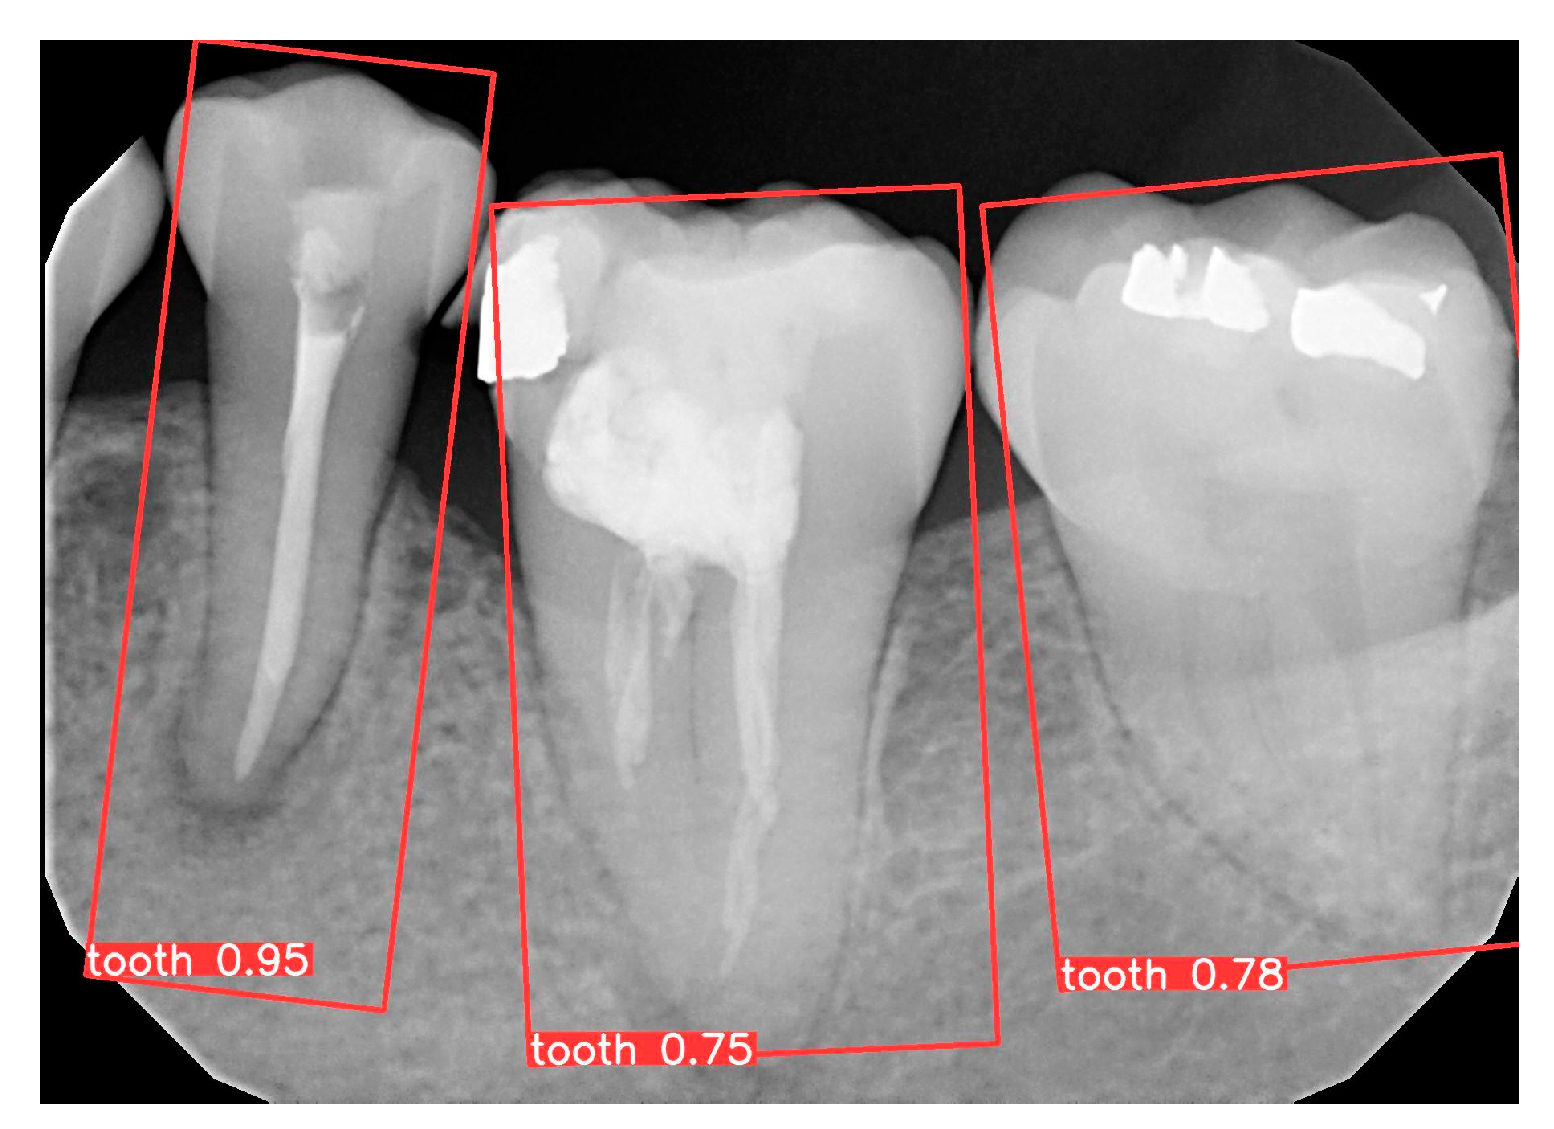

3.1. YOLO Detection and Image Segmentation